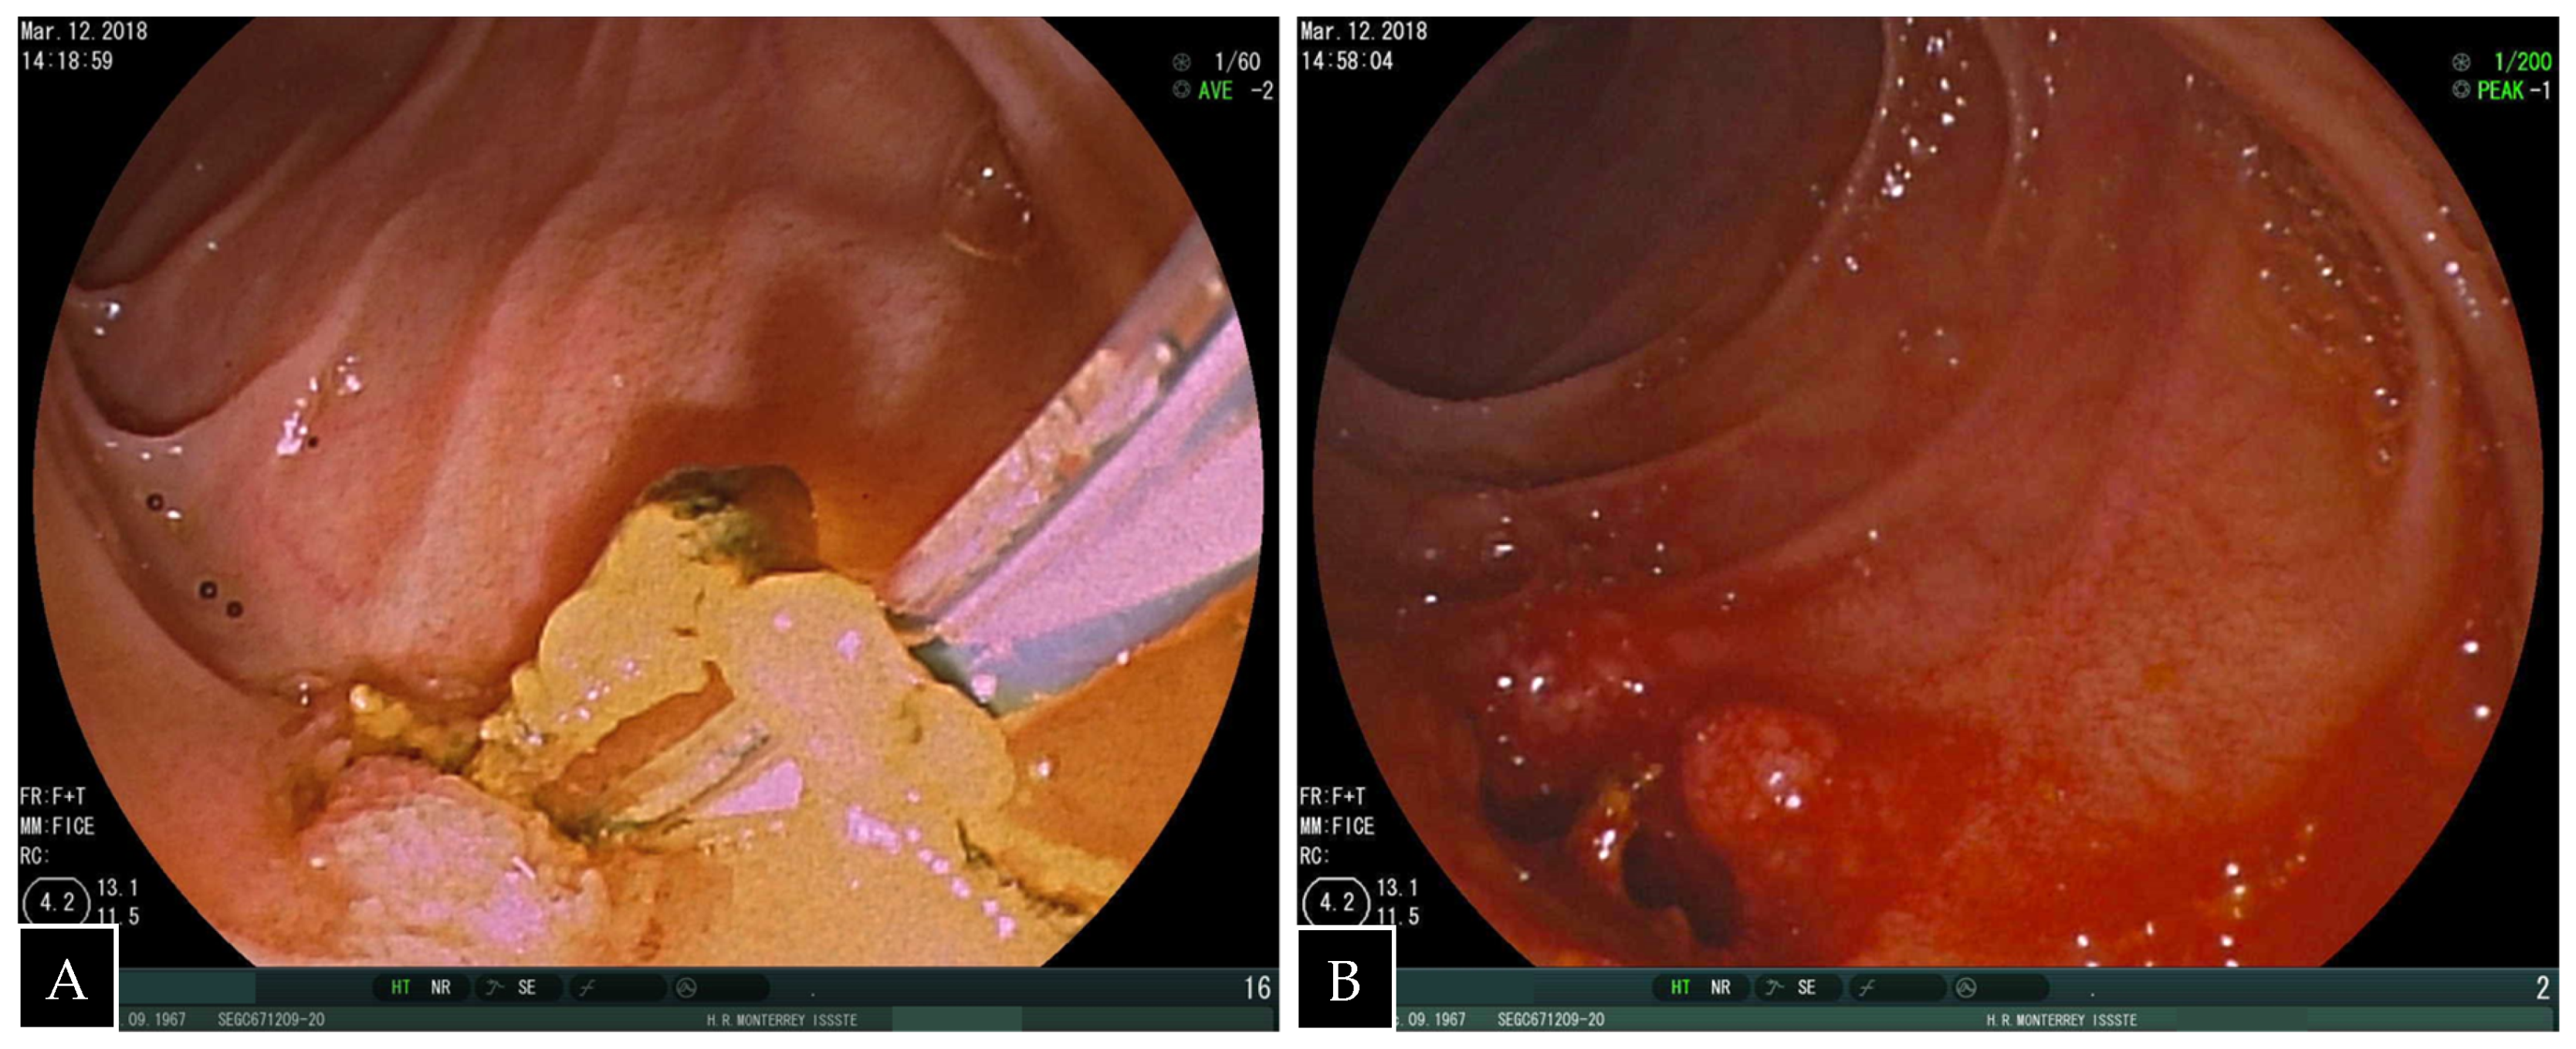

Figure 4.

(A) Endoscopic view of the duodenum showing retrieval of biliary sludge and stones and (B) dilated bilioenteric anastomosis.

A standard side-viewing endoscope (Olympus TJF 160 VR or TJF 145, Tokyo, Japan) was advanced through the jejunal trocar in caudocephalad direction until the papilla was visualized. Once successful catheterization of the papilla was obtained, ERCP was carried out in a standard fashion showing a filling defect in the common hepatic duct proximal to the anastomosis. Balloon dilation of the anastomosis was required (Figure 3). A single 5 mm stone and biliary sludge were removed with a retrieval balloon catheter. Subsequent cholangiography showed no evidence of filling defect. The enterotomy was closed with continuous sutures in double layer (Figure 4). There were no incidents during the surgical procedure.